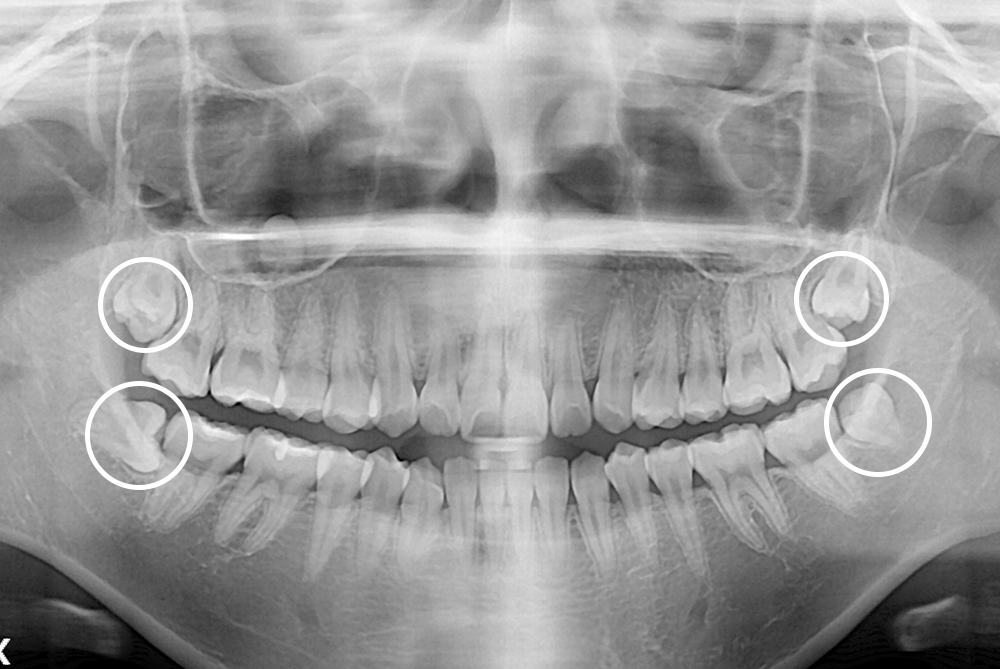

[사랑니] 매복 사랑니 발치

치료후 : 2018-09-12

세종치과는 구강악안면외과학 박사이신 원장님이 발치하는 치과입니다.